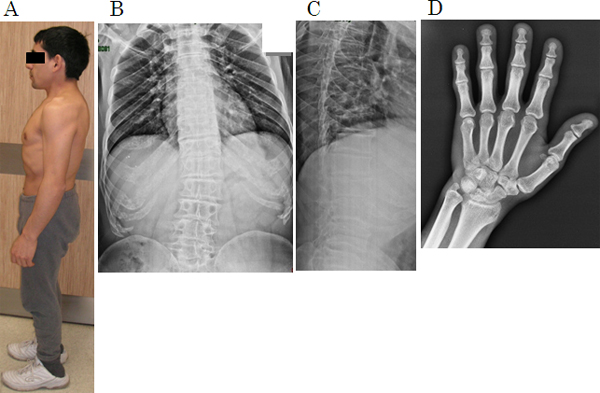

図1 1型短体幹症の病態(29歳、男性患者)

Aは外観、B~DはX線画像。

- A: 短体幹型(胴体が短くなるタイプ)の低身長(135cm)。相対的に手足が長く見える。四肢の奇形等はない。

- B: 脊椎正面像。疾患による脊椎の発達障害のために、脊椎椎体の高さが低くなっている。軽度の側弯変形、肋骨の早期石灰化も見られる。

- C: 脊椎側面像。脊椎椎体は扁平で、長方形になっている。椎間板の幅が狭くなっている。早期の椎間板変成症の像である。

- D: 左手正面像。中手骨の短縮がみられる。